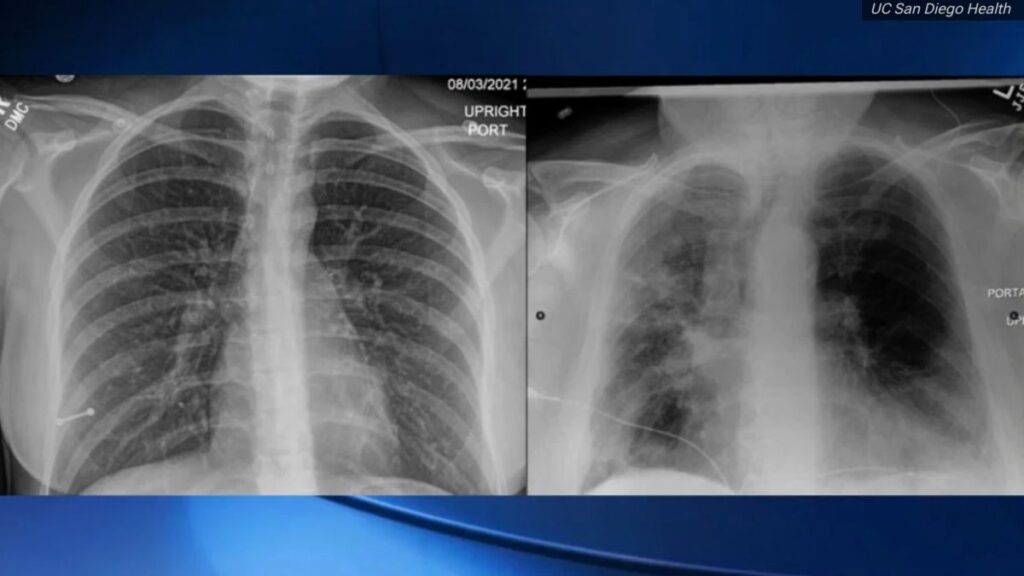

El doctor Tim Morris, un especialista en pulmones y en terapia intensiva de la Universidad de San Diego, dijo que no es necesaria una capacitación técnica para ver la diferencia: en la izquierda están los pulmones de una persona vacunada contra el COVD-19 y en la derecha, la del paciente no vacunado, según reporta NBC Bay Area.

La radiografía de la izquierda muestra muchas más zonas oscuras lo cual es normal y significa que los pulmones están llenos de aire, según el doctor Morris.

Mientras que la radiografía del paciente no vacunado muestra más zonas grises, más nubladas, lo que quiere decir que los pulmones presentan infecciones.

‘’Esa es una señal de neumonía del COVID-19’’, dijo sobre el paciente no vacunado mientras que la radiografía del paciente vacunado muestra a la vacuna en funciones.